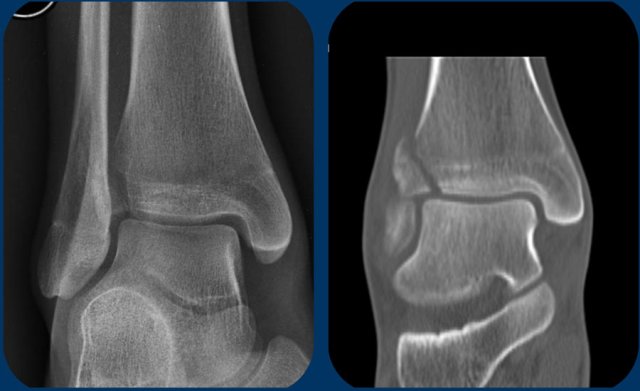

Images

On the AP-view and the coronal CT-reconstruction we see a Tillaux fracture as stage 1. No other fracture was seen.

Study these images. You may have to click on them to get a larger view.